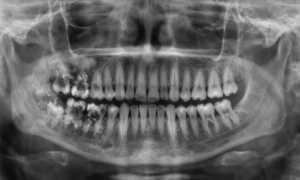

B. OPG (Orthopantomogram)

Sometimes, the infection is not limited to one tooth.

An OPG is a wide-angle X-ray that scans your entire upper and lower jaw, including all teeth, sinuses, and jaw joints, in a single image.

1. Purpose: To see if the Alveolar Abscess has spread to neighboring teeth or into the maxillary sinus (for upper teeth) or the mandibular nerve canal (for lower teeth).

Unlike many clinics that refer you to a diagnostic centre, we have an In-House OPG Machine. You get scanned and diagnosed immediately in the same appointment.